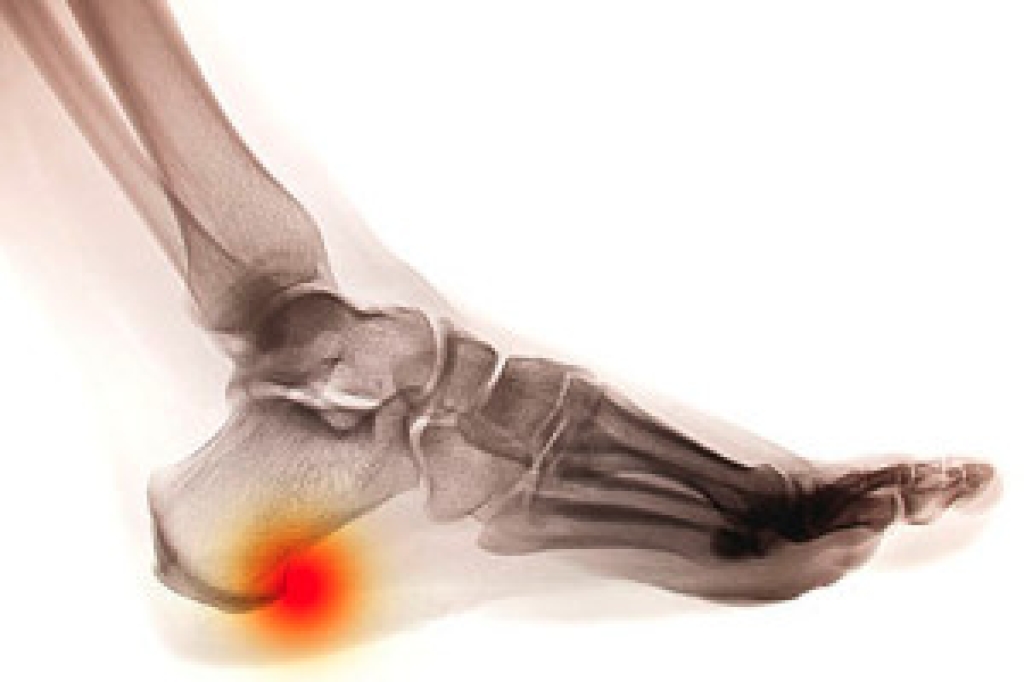

Heel spurs are formed by calcium deposits on the back of the foot where the heel is. This can also be caused by small fragments of bone breaking off one section of the foot, attaching onto the back of the foot. Heel spurs can also be bone growth on the back of the foot and may grow in the direction of the arch of the foot.

The pain associated with spurs is often because of weight placed on the feet. When someone is walking, their entire weight is concentrated on the feet. Bone spurs then have the tendency to affect other bones and tissues around the foot. As the pain continues, the feet will become tender and sensitive over time.